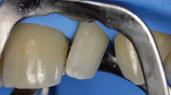

Composite Restorations in the Anterior Region

Restoring anterior teeth with large defects using composite seems to be quite challenging. With high-performance materials at hand and a systematic layering concept in mind, however, it is possible to produce highly aesthetic results in a reproducible way. The clinical case below is used to illustrate a dual-shade layering technique with CLEARFIL MAJESTY™ ES-2 Premium, a composite system with pre-defined colour combinations.

Case Example

The patient, a young male, was unhappy with the appearance of his maxillary anterior teeth. Several years ago, his central incisors had been restored with composite. These existing restorations had defective and heavily discoloured margins, while their shade did not match the adjacent natural tooth structure. The maxillary lateral incisors were peg-shaped (microdontia). Economic considerations and the desire to save as much natural tooth structure as possible made the team decide to restore all four maxillary incisors with composite. CLEARFIL MAJESTY™ ES-2 Premium became the material of choice as it eliminates the need for complicated shade combination formulas and supports predictable outcomes.

Restoring The Central Incisors

We decided to restore the central incisors first and then focus on the lateral incisors. The tooth shade was determined using the VITA™ classical A1-D4 shade guide, while composite buttons were applied to the teeth to verify the determined shade combination. In order to simplify the restoration procedure, a palatal silicon index was produced before removing the existing restorations.

Fig. 2 Intraoral image of the initial situation with defective composite restorations and microdonts. Two composite buttons on the right lateral incisor are used to verify the determined shade combination.

Fig. 3 Central incisors after removal of the old restorations and the beveling of the enamel.

During minimally invasive tooth preparation, bevels were created at the margins to provide for a smooth optical transition from the natural tooth structure to the composite.

An adhesive (CLEARFIL™ Universal Bond Quick) was applied after selective etching of the enamel to achieve a strong bond. With the aid of the silicon index, it was easy to create the palatal shells of the restorations with CLEARFIL MAJESTY™ ES-2 Premium in the shade A3E (enamel), which matches the determined tooth shade A3. The dentin core was built up with the same composite in the recommended shade A3D (dentin), mamelons were modelled and some CLEARFIL MAJESTY™ ES-2 Premium in the shade WD added for the incisal halo, while some individual effects (like enamel cracks) were imitated with brown stain. The build-up was finalized in the interproximal and labial areas with composite in the shade A3E. Between the central incisors, a wedge was used to retract the papilla and facilitate the designing of the interproximal contact area. The finished and pre-polished restorations already had a natural appearance.